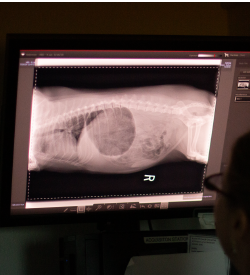

When your veterinarian needs more information for diagnostic purposes, they may call for x-rays. X-rays provide views of the musculoskeletal system, and work by passing x-ray waves through the body, and taking snapshots of their distribution. X-rays are a completely safe and non-invasive procedure, and are useful for diagnosing fractures, tumors, infections, and deformities. They are often used in both routine and emergency procedures.

At Broadway Veterinary Clinic, we use digital x-rays instead of traditional film x-rays for the benefit of our patients. The benefits of digital x-rays include: